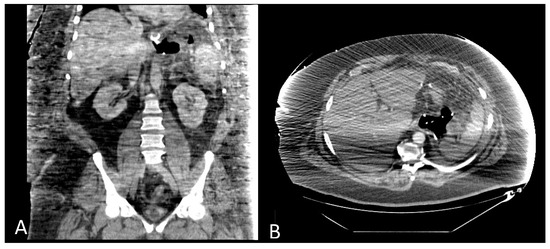

- Dugan, J.; Bajwa, K.; Singhal, S. Endoscopic removal of gastric band by use of a stent-induced erosion technique. Gastrointest. Endosc. 2016, 83, 654–655. [Google Scholar] [CrossRef]

- Manos, T.; Nedelcu, A.; Noel, P.; Zulian, V.; Danan, M.; Vilallonga, R.; Carandina, S.; Nedelcu, M. Endoscopic Gastric Band Removal. J. Clin. Med. 2023, 12, 617. [Google Scholar] [CrossRef] [PubMed]

- Di Lorenzo, N.; Lorenzo, M.; Furbetta, F.; Favretti, F.; Giardiello, C.; Boschi, S.; Alfredo, G.; Micheletto, G.; Borrelli, V.; Veneziani, A.; et al. Intragastric gastric band migration: Erosion: An analysis of multicenter experience on 177 patients. Surg. Endosc. 2013, 27, 1151–1157. [Google Scholar] [CrossRef] [PubMed]